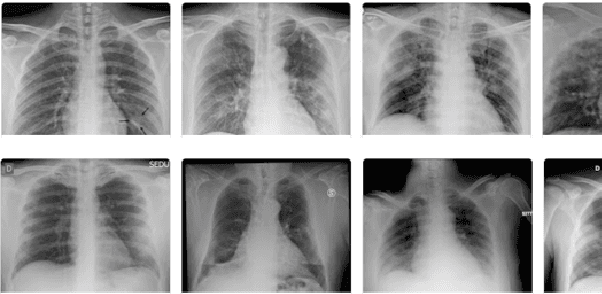

Abstract:Covid-19 detection at an early stage can aid in an effective treatment and isolation plan to prevent its spread. Recently, transfer learning has been used for Covid-19 detection using X-ray, ultrasound, and CT scans. One of the major limitations inherent to these proposed methods is limited labeled dataset size that affects the reliability of Covid-19 diagnosis and disease progression. In this work, we demonstrate that how we can augment limited X-ray images data by using Contrast limited adaptive histogram equalization (CLAHE) to train the last layer of the pre-trained deep learning models to mitigate the bias of transfer learning for Covid-19 detection. We transfer learned various pre-trained deep learning models including AlexNet, ZFNet, VGG-16, ResNet-18, and GoogLeNet, and fine-tune the last layer by using CLAHE-augmented dataset. The experiment results reveal that the CLAHE-based augmentation to various pre-trained deep learning models significantly improves the model efficiency. The pre-trained VCG-16 model with CLAHEbased augmented images achieves a sensitivity of 95% using 15 epochs. AlexNet works show good sensitivity when trained on non-augmented data. Other models demonstrate a value of less than 60% when trained on non-augmented data. Our results reveal that the sample bias can negatively impact the performance of transfer learning which is significantly improved by using CLAHE-based augmentation.